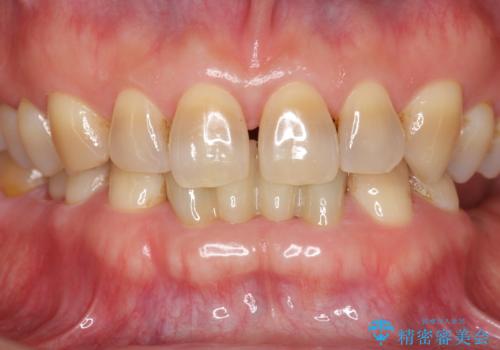

セラミックも強い衝撃で欠けないわけではないため、強度のあるフルジルコニアクラウンでブリッジを作成しました。

フルジルコニアクラウンはやや白すぎるといった難点がありますが、今回は強度を優先することにしました。